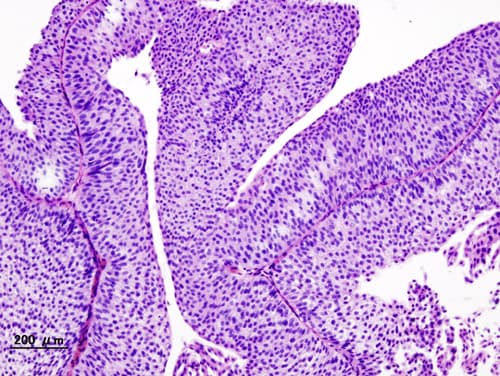

La paroi interne de la vessie est tapissée de cellules transitionnelles qui sont à l'origine de la plupart des cancers de la vessie. L'évolution et la prise en charge dépend beaucoup du caractère invasif de la tumeur. On distingue le cancer superficiel de la vessie du cancer invasif (tumeur infiltrante). Si le cancer superficiel reste de bon pronostic, le cancer invasif de la vessie est beaucoup plus grave et nécessite des traitements agressifs. Il s'agit de l'un des dix plus fréquents cancers avec un peu plus de 500 000 cas annuels de par le monde. L'âge moyen est de 65 ans. Il touche 4 hommes pour 1 femme, mais ce taux évolue au fur et à mesure que l'impact du tabagisme chez la femme se fait sentir. Le cancer de la vessie est une tumeur fréquente. En 2000, cas ont été diagnostiqués en France, parmi lesquels un tiers est lié au tabagisme. Il est le sixième cancer le plus fréquent en France. Il représente 3,5 % des décès par cancer. Le taux de survie à 5 ans est de 96 %, lorsque les tumeurs infiltrent le muscle uniquement (TVIM), 70 % lorsqu'il s'étend et seulement 5 % lorsque les métastases se diffusent dans le corps. Tous types de cancers de la vessie confondus, le taux de survie à 5 ans est de 77,4 % . Il est plus mauvais chez la femme en raison d'un retard au diagnostic, l'hématurie étant banale au cours d'une infection urinaire.. Le facteur de risque non modifiable le plus important reste l'âge. Les facteurs favorisants les plus importants sont le tabagisme (responsable de 40 % des cancers de la vessie) et certains cancérogènes chimiques. À ce titre le cancer de la vessie peut être considéré comme une maladie professionnelle. Les principales substances industrielles en cause sont : les amines aromatiques ; leurs dérivés hydroxylés halogénés et sulfonés.